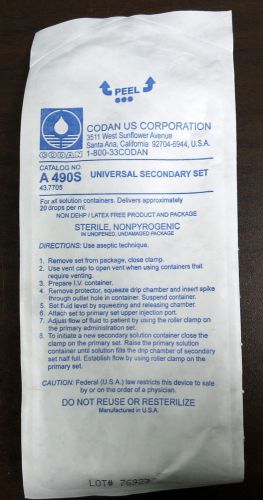

Codan US A490S Universal Secondary Set (Lot of 13)